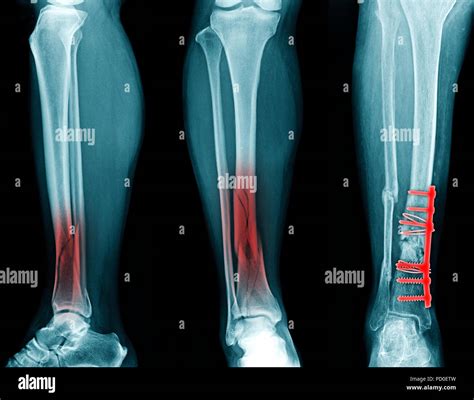

Diagnosing a Broken Fibula and Tibia

Diagnosing a fracture involves a combination of physical examination and imaging tests. The process typically includes:

• Physical Examination: A healthcare provider will assess the injured area for swelling, deformity, and tenderness.

• X-rays: These are the primary imaging tool used to confirm the presence and type of fracture.

Treatment Options for a Broken Fibula and Tibia

The treatment for a fibula and tibia broken depends on the severity and type of fracture. Common treatment options include:

• Immobilization: Using a cast, splint, or brace to keep the bone in place while it heals.

• Surgery: In severe cases, surgery may be required to realign the bones and stabilize them with plates, screws, or rods.